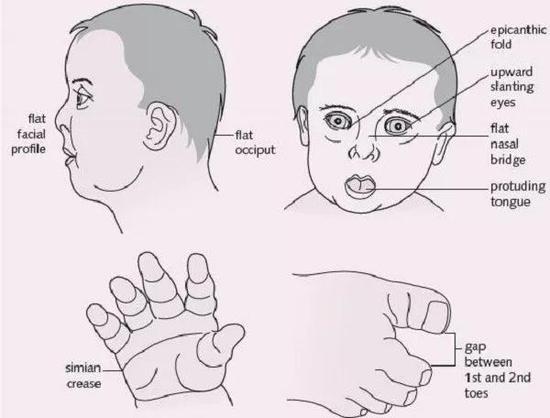

平坦而宽阔的脸庞、扁塌鼻梁、倾斜的眼睛、突出的舌头

唐氏综合征患者通常具有相似的面容特征。

而且不分国界地巧妙契合。

因此这个群体也获得了“国际脸”这个容易让人误会的称号。